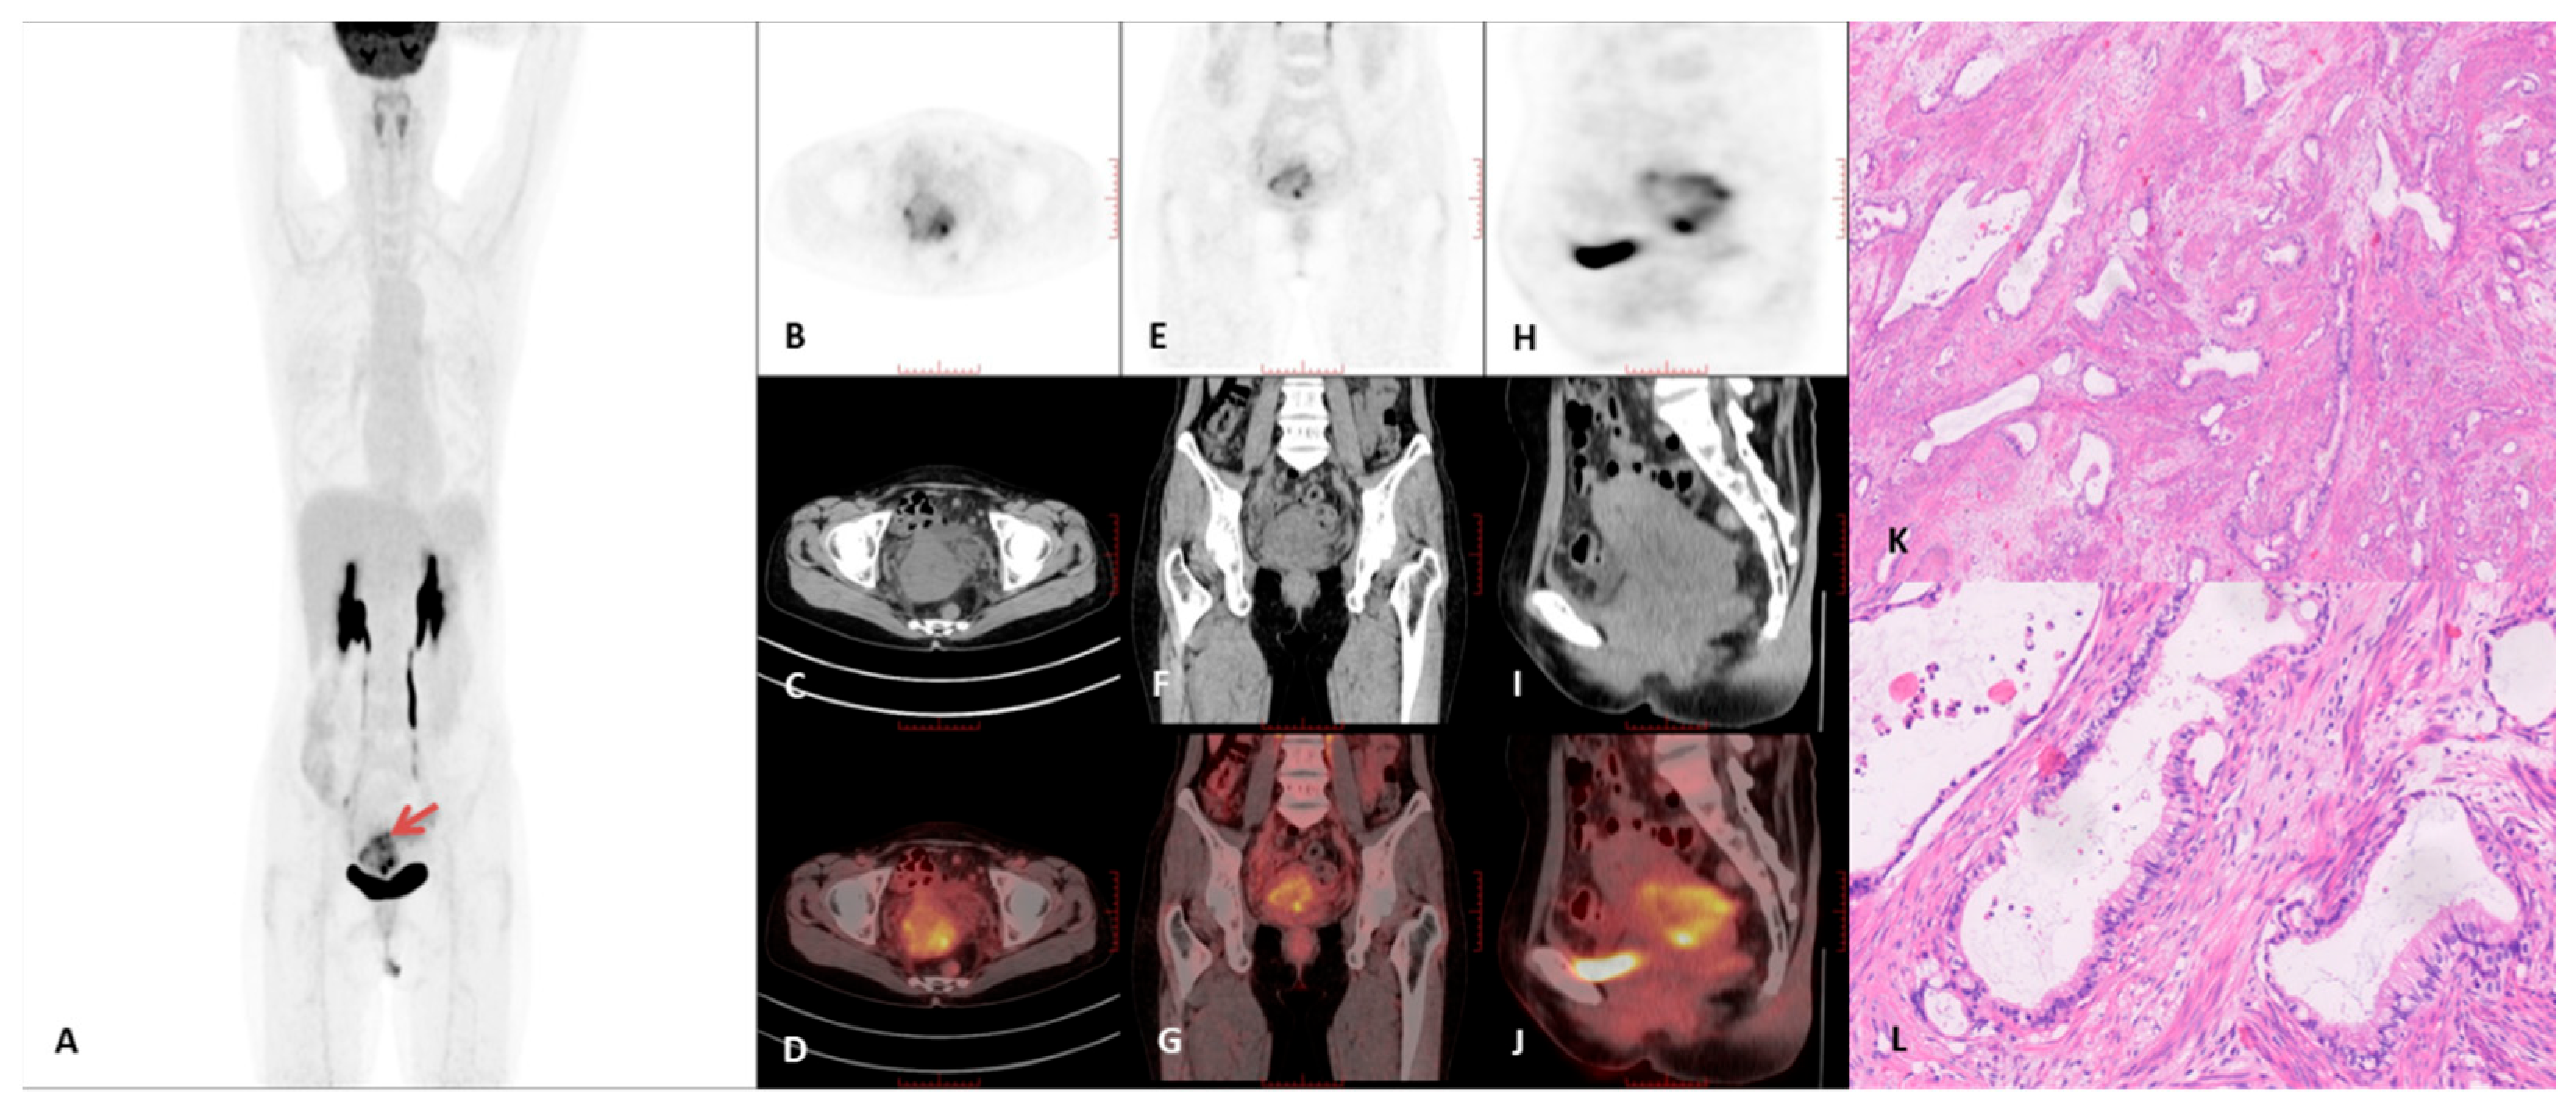

3.2. PET/CT Imaging Characteristics

| Case # | FIGO 2018 | Tumor Diameter Mean Value (cm) | Macrocysts | Tumor Growth Pattern | Intrauterine Fluid | SUVmax | T/L SUVmax |

|---|---|---|---|---|---|---|---|

| 1 | IVB | 2.9 | Present | Diffuse | Present | 3.0 | 1.0 |

| 2 | IVA | 2.4 | Present | Diffuse | Present | 2.8 | 1.1 |

| 3 | IB | 3.7 | Present | Diffuse | Present | 2.6 | 0.8 |

| 4 | IVB | 6.5 | Present | Diffuse | Present | 9.3 | 3.9 |

| 5 | IVB | 3.3 | Present | Mass | Present | 9.7 | 2.7 |

| 6 | IIIC | 4.8 | Present | Diffuse | Present | 11.6 | 3.1 |

| 7 | IIA | 4.6 | Present | Diffuse | Present | 6.8 | 1.7 |

| 8 | IVB | 2.9 | Present | Diffuse | Present | 12.6 | 3.8 |

| 9 | IVB | 5.2 | Microcysts | Diffuse | Present | 6.2 | 1.9 |

| 10 | IVB | 5.9 | Present | Diffuse | Absent | 13.3 | 6.0 |

| 11 | IVB | 6.8 | Present | Diffuse | Present | 7.7 | 3.1 |

| 12 | IVB | 3.7 | Present | Diffuse | Present | 4.5 | 1.2 |